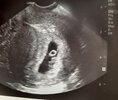

Powiedzcie, czy tylko ja jestem taka szalona, ze pierwszą wizytę u lekarza będę mieć w 6+3? 🙈 mam wrażenie, ze Wy cały czas macie wizyty tylko ja czekam nie wiadomo na co 😂 chyba znów robię coś źle 🤣

Ja się umówiłam na 7+0 tj 07.04. Na 18.00 w wielki piątek. Rok temu o 17.36 w wielki piątek urodziłam 🤣 na becie w tej ciąży nie byłam. Zrobiłam tylko 3 testy ( czwartek, sobota i dziś, ładnie ciemnieją wiec czekam już na wizytę)

Nie wierze 😭♥️

ROŚNIJ mój dzidziulku zdrowy ROŚNIJ ♥️

w piatek było 36😍

Będzie idealnie! Ja miałam pierwsza 6+5, wg usg wyszło 6+3 i pieknie biło już serducho :)